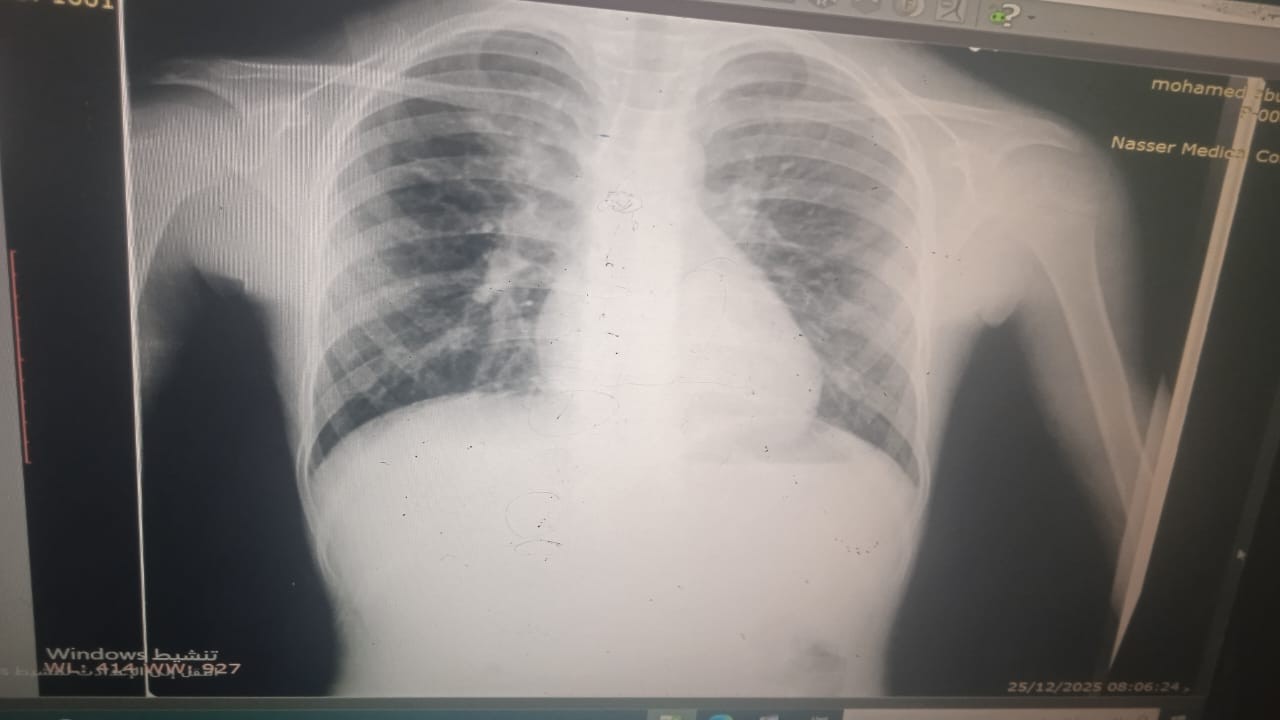

يقول والده، إن ابنه وُلد مصابًا بتشوّه خلقي يُعرف باسم "رباعية فالوت"، موضحًا أن حالته تتضمن ثقبًا متوسط الحجم بين البطينين، وضيقًا شديدًا في الصمام الرئوي، وتضخمًا في عضلة القلب اليمنى، وانحرافًا بالشريان الأورطي إلى الجهة اليمنى.

ويؤكد الوالد، أن حالة ابنه مصنّفة "A طارئ"، وأن وضعه الصحي تدهور خلال الحرب، حيث يعاني التهابات صدرية شديدة بشكل دائم، وضيقًا في التنفس، وإرهاقًا متكررًا، إضافة إلى حاجته لاستخدام البخاخ بشكل مستمر، وتعرضه لتشنجات.